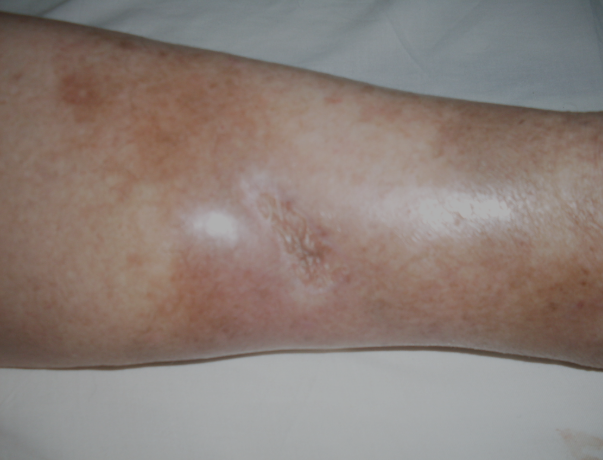

ÚLCERA VARICOSA - caso 22

Que Úlceras Varicosas são, em sua maioria, lesões de perna que todos nós “conhecemos”. São pacientes que vivem sofrendo dor com feridas enfaixadas e tratando, sem sucesso, ao longo de anos que geralmente nunca cicatrizam.

A incidência é grande, principalmente em pessoas acima dos 60 anos, portadoras de varizes dos membros inferiores.

Em sua maioria é causada por insuficiência vascular nos membros, associada á quadros repetidos de streptococcia e por falta de tratamento adequado no inicio do problema.

Não é contagiosa. Porém, as lesões geralmente são crônicas e infectadas por infecções secundárias com grande produção de secreção e odor fétido, que pioram com as áreas de necrose, levando algumas pessoas a se “isolarem” ou se afastarem destes pacientes, tratando-os de forma discriminativa.